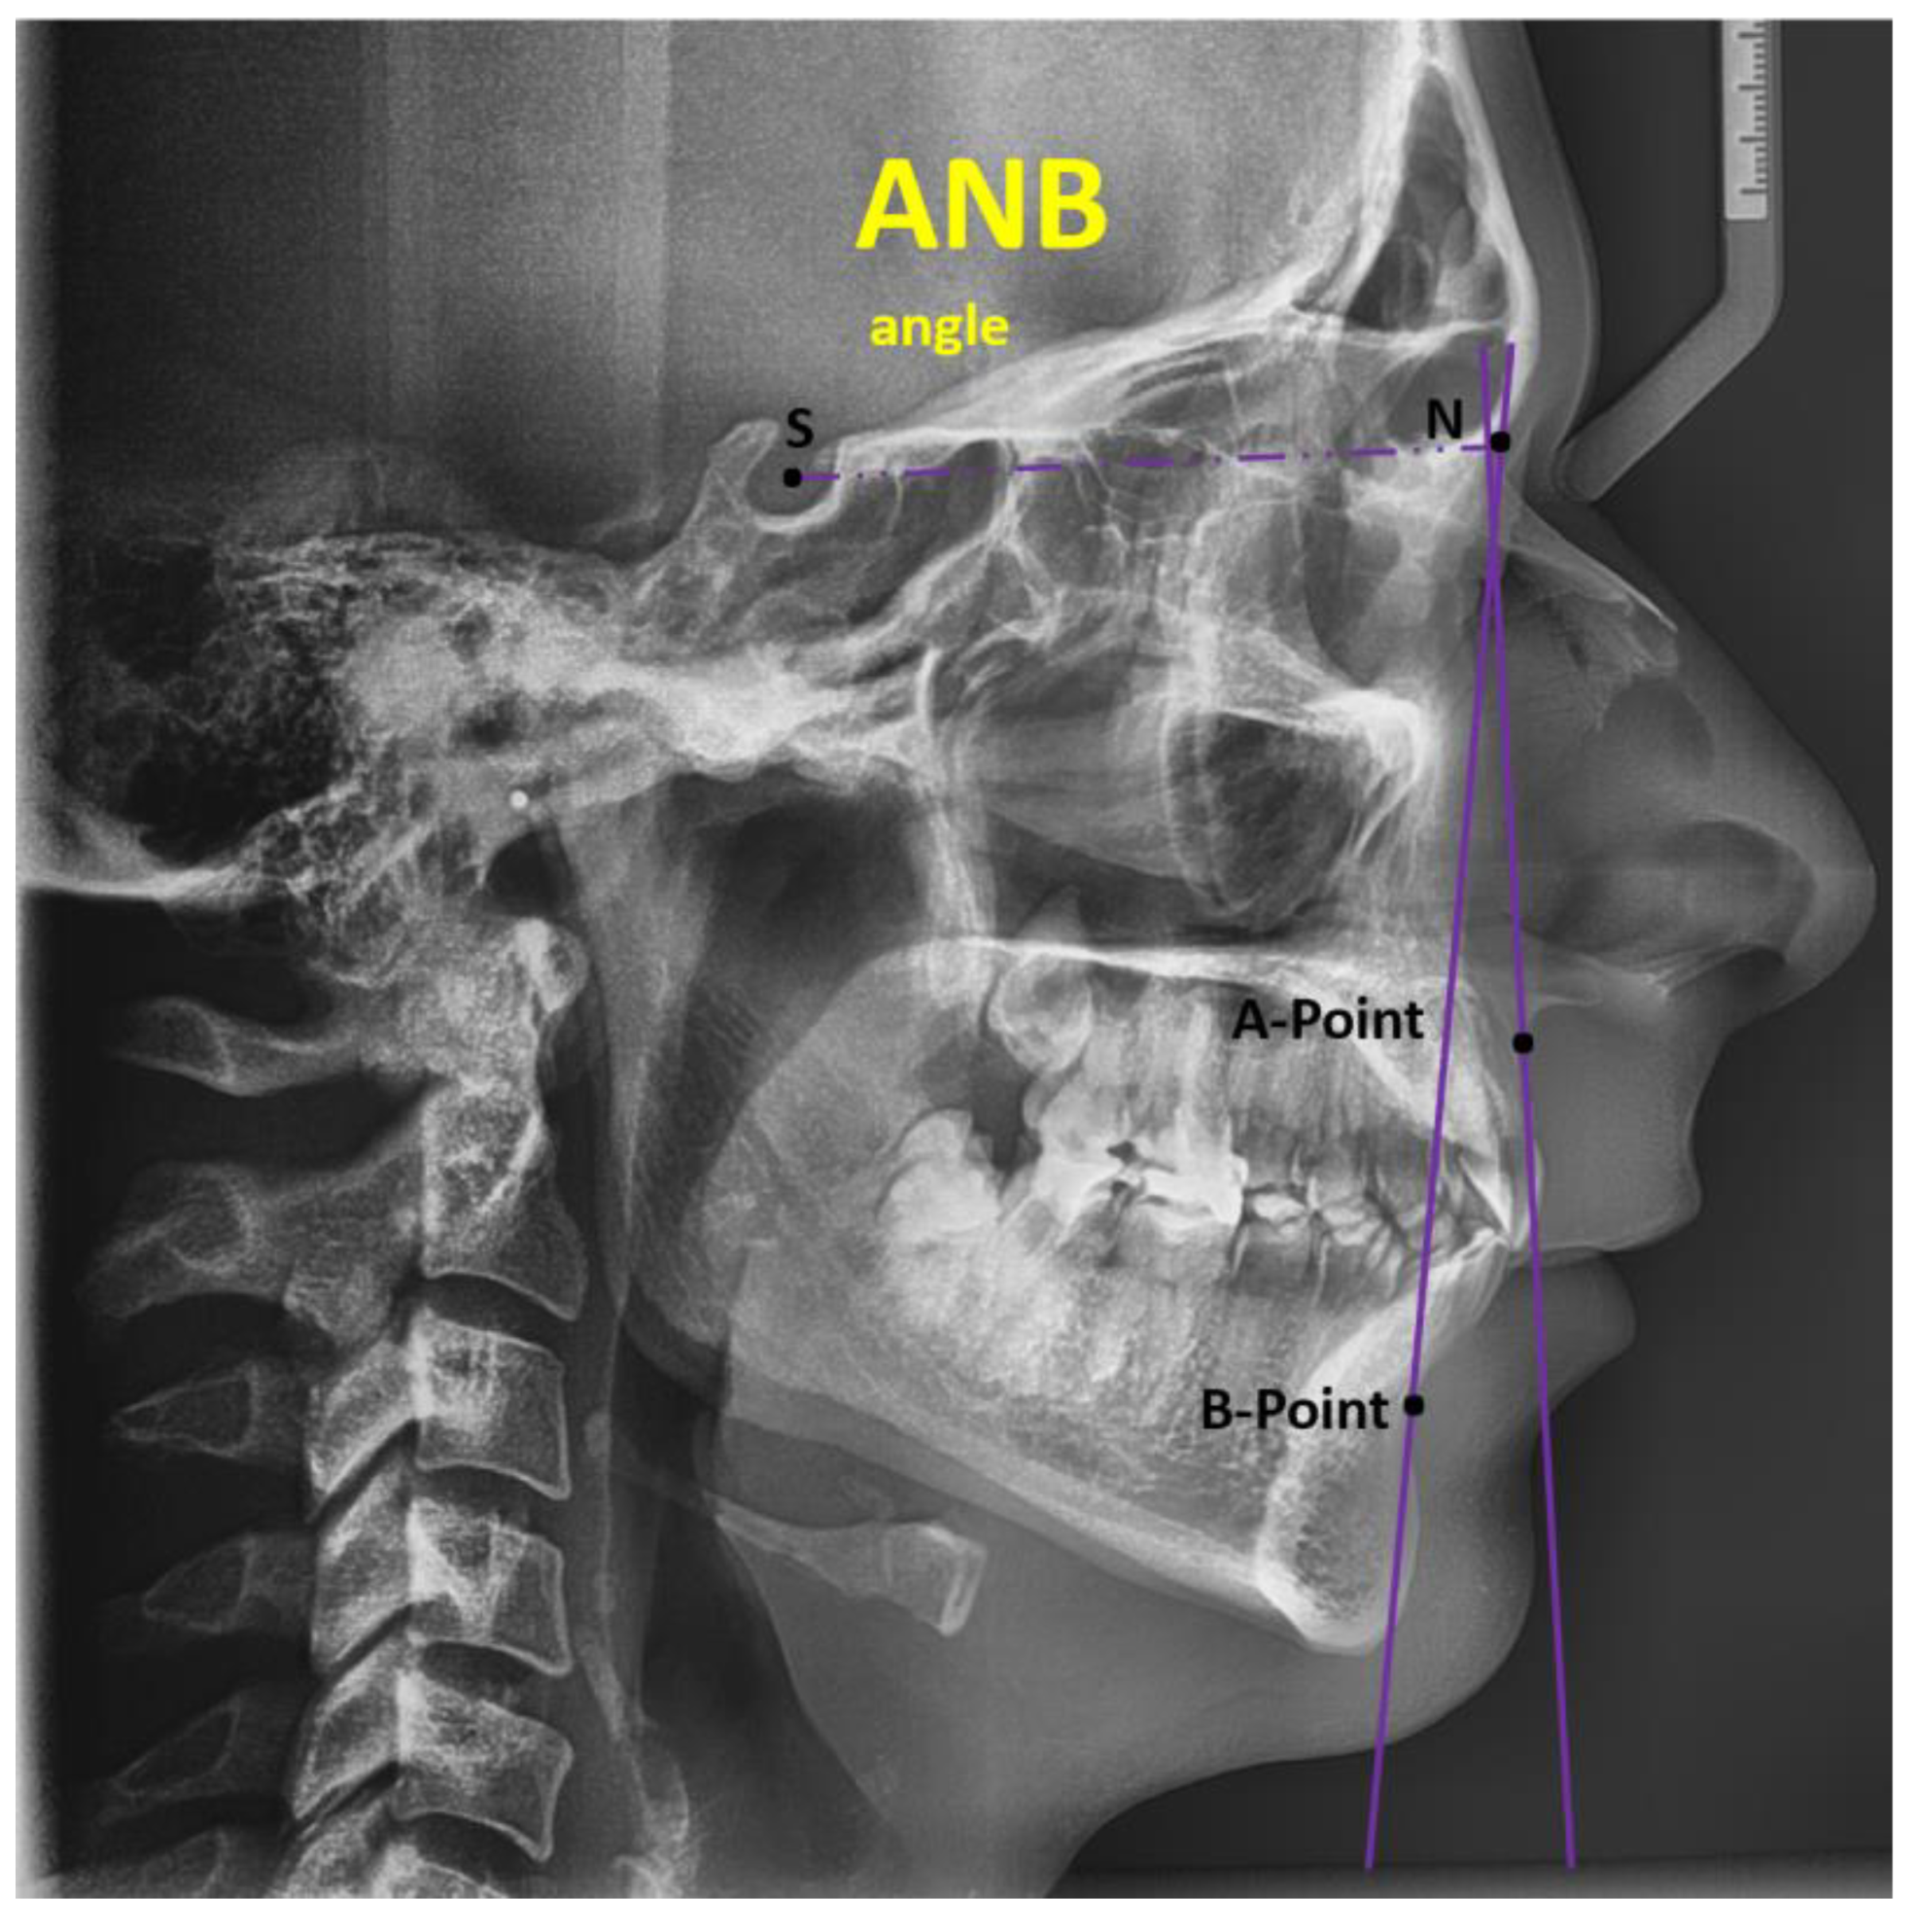

2.1.1. Digital Lateral Cephalometric Measurements and Protocol